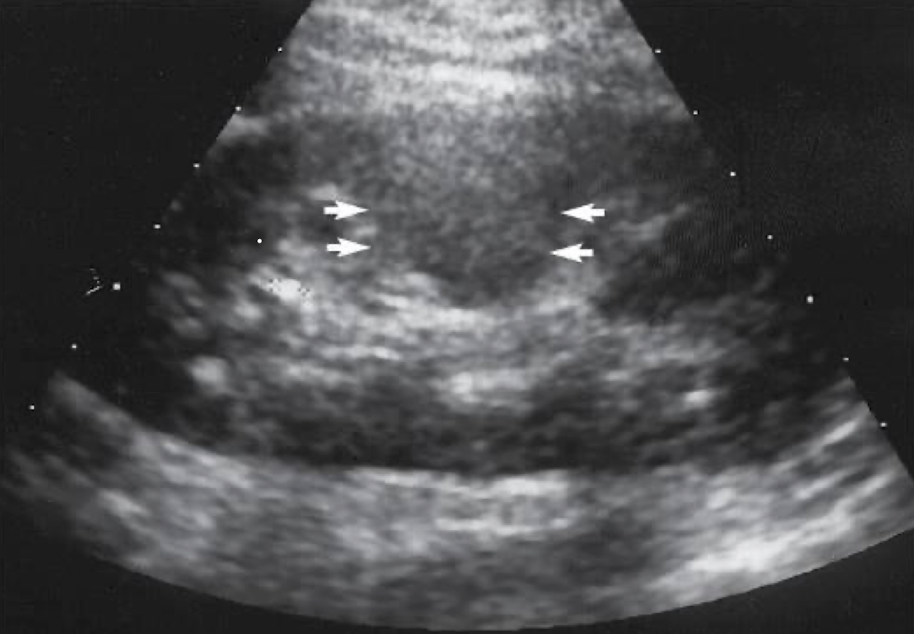

SONO: autosomal recessive polycystic kidney disease (ARPKD)

enlarged echogenic (cortex and medulla) kidneys with microscopic or small cysts

lack corticomedullary differentiation (can’t tell difference between cortex and medulla)